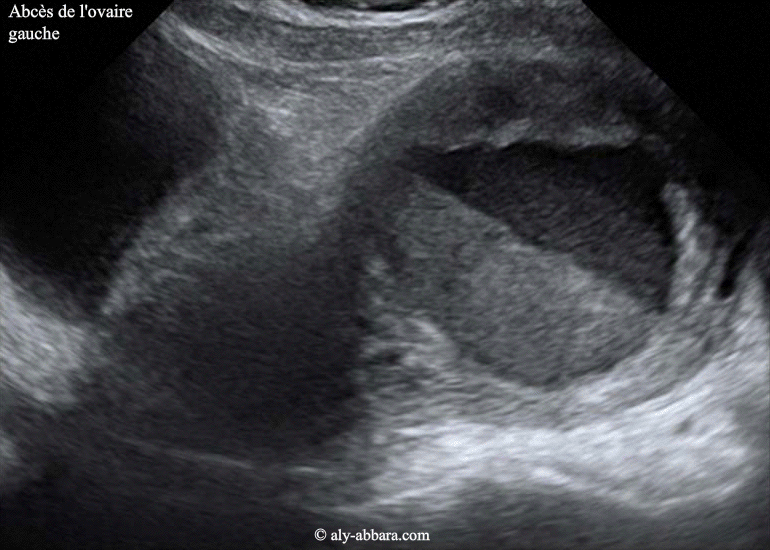

Image animée montrant un des aspects échographiques d'un ovaire gauche porteur d'un abcès à évolution lente, associé à une salpingite aiguë homo-latérale se manifestant par la formation d'un (pyosalpinx). Il s'agit d'une poussée aiguë d'infection génitale haute sur une infection génitale haute chronique (avec un hydrosalpinx droit). Voir l'aspect de cette pathologie infectieuse au scanner |

| Sur ces images on met en évidence la présence d'une formation kystique intra-ovarienne gauche mesurant 74 x 56 x 71 mm (soit 155 cm3), uniloculaire, à contenu hypo-échogène avec un aspect de niveau faisant penser à la présence d'un contenu liquidien à deux niveaux de densité. Les structures ovariennes entourant cette formation ovarienne kystique paraissent épaissies, infiltrées et contenant des multiples petites formations kystiques satellites. Échographiquement, l'ovaire droit est normal, avec un volumineux hydrosalpinx droit. Cliniquement, on note la présence d'une masse palpable dans la région sous ombilicale, de 8 à 10 cm de diamètre, légèrement sensible, chez une patiente âgée de 28 ans, souffrant d'une douleur abdominale sous ombilicale, évoluant depuis une semaine, sans hyperthermie, mais biologiquement on note la présence d'une hyperleucocytose à 14 giga/l, et CRP à 186 mg/l et enfin, une anémie inflammatoire à 7 g/dl. Le scanner abdomino-pelvien confirme la présence de masse à cavité uniloculaire en position très haute, surplombant le fond utérin et au contact avec la paroi abdominale antérieure, dans la région qui se trouve au-dessous de l'ombilic. Au voisinage de l'ovaire gauche abcédé, on remarque la présence d'une autre formation oblongue, à paroi infiltrée, avec dans son centre, une collection liquidienne ; il s'agit de la trompe gauche inflammatoire avec petit pyosalpinx. Le diagnostic évoqué est celui d'une infection génitale haute gauche comportant un abcès ovarien et un pyosalpinx gauches. Le diagnostic définitif a été réalisé suite à la réalisation d'une laparotomie : volumineux ovaire gauche abcédé et collant fortement, par des adhérences, anciennes denses et fibreuses, à la paroi abdominale antérieure et aux anses grêles juxtaposées. La cavité de l'ovaire est suppurée, ainsi les multiples formations folliculaires satellites, intra-ovarienne. La trompe gauche est très inflammatoire à contenu suppuré (pyosalpinx). L'ovaire droit est normal. La trompe droite est caractérisée par la présence de multiples signes macroscopiques de salpingite ancienne (non aiguë) : obturation l'ostium tubaire externe ; un volumineux hydrosalpinx et multiples voiles adhérentiels. Le cul-de-sac postérieur est bloqué par de vieilles adhérences fibreuses. L'examen de contrôle un mois plus tard, montre l'aspect de cet ovaire gauche où on note la disparition complète de la cavité abcédée intra-ovarienne gauche, ainsi la pyosalpinx gauche et l'hydrosaplinx droit. |